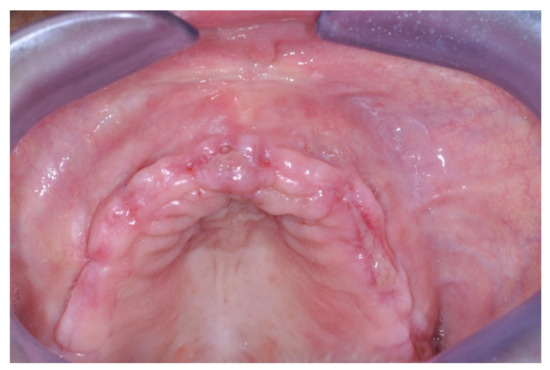

Patients rinsed with a chlorhexidine mouthwash (0.2%) for 1 min immediately prior to the intervention. Local anesthesia were administered using mepivacaine with adrenaline at ratios of 1:100,000 or 1:50,000. Crestal incisions were made with releasing incisions far away from the future membrane positioning and full thickness flaps were elevated. After the meticulous removal of all residual soft tissues in the regenerating site, copious bleeding was induced using a bone scraper (Safescraper Curve TWIST, META, Reggio Emilia, Italy) (Figure 1). A prosthetically guided implant placement was performed following the instructions of manufacturer (Thommen Medical, Grenchen, Switzerland). Only 1 patient had implants placed 9 months after bone augmentation because the initial bone thickness did not permit the primary stabilization of the implant fixtures (Figure 2, Figure 3, Figure 4, Figure 5, Figure 6, Figure 7 and Figure 8).

Figure 2. Sequence of treatment phase of the only patient who was treated according a 2-stage approach: stage 1 GBR procedure and stage 2 implant placement (pre-operative view).

Figure 3. Intra-surgical view prior to horizontal GBR.